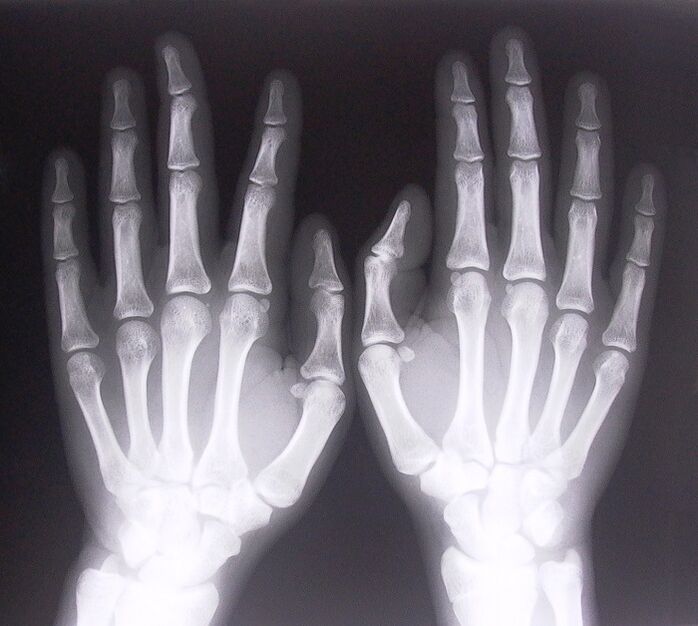

- Ligamentite estenosante. Para identificar a causa da doença, é necessária uma radiografia. Os sintomas são típicos: movimento doloroso da mão, rotação da palma cerrada. Além disso, durante a extensão, geralmente são ouvidos cliques.

Para começar a tratar dores nas articulações dos dedos, você precisa determinar corretamente qual doença as causou. Para determinar que tipo de doença afeta uma pessoa que sente dores nas articulações ao dobrar os braços, os médicos recomendam realizar os seguintes procedimentos:

- Faça radiografias.

Se houver dor nas articulações ao dobrar os dedos, você não deve esperar uma solução para o problema em si. Ao não consultar o médico a tempo, a pessoa desenvolve a doença, que traz consequências muito graves. Muitas vezes a mobilidade dos dedos é reduzida e, no futuro, pode surgir um problema como a inflexibilidade absoluta do dedo. Tais consequências às vezes levam uma pessoa a ficar com deficiência.